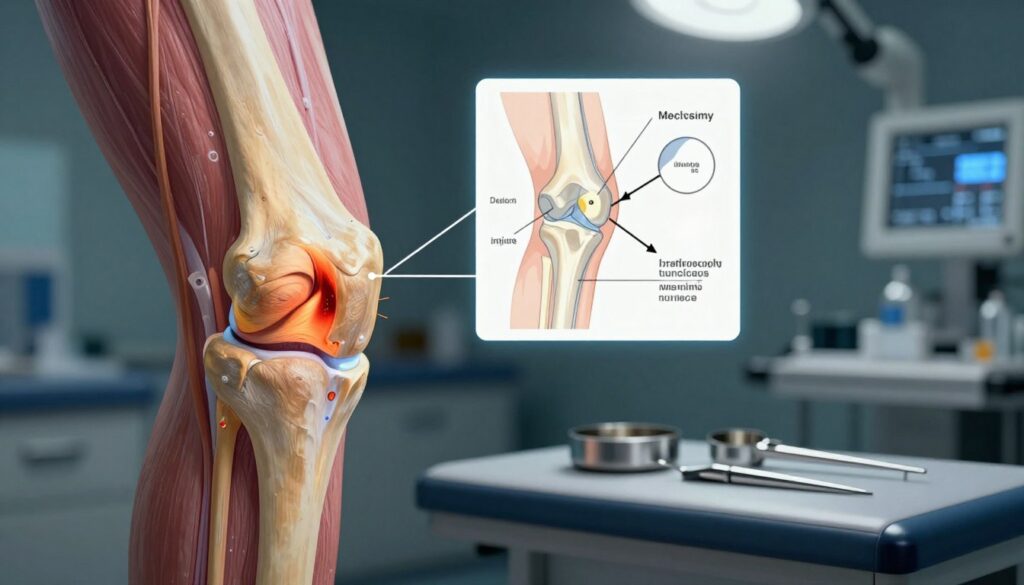

Zabieg polega na wprowadzeniu kamery i mikronarzędzi przez kilka niewielkich nacięć. Dzięki temu lekarz ogląda obraz wnętrza stawu na monitorze, a pole widzenia poprawia płukanie roztworem soli fizjologicznej.

To metoda małoinwazyjna, używana zarówno diagnostycznie, jak i leczniczo. Lekarz może zobaczyć uszkodzenia łąkotek, więzadeł, chrząstki, ciała obce czy przerost błony maziowej i od razu podjąć naprawę.

Skręcenie, nagły zwrot lub upadek to typowe mechanizmy urazowe. W praktyce kończą się one często pęknięciami lub rozwarstwieniami łąkotek, zerwaniami więzadeł (szczególnie ACL) oraz uszkodzeniami chrząstki.